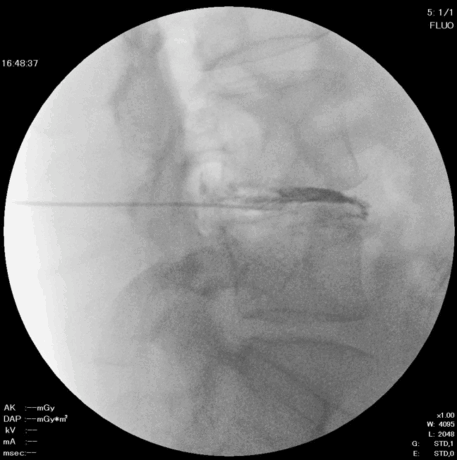

3. 髄核の一部摘出

グラスパー鉗子を用いて、椎間板内部の髄核を一部取り出します。

4. ラジオ波焼灼(アブレーション)

留置針にデバイスを挿入し、ラジオ波で焼灼を行います。